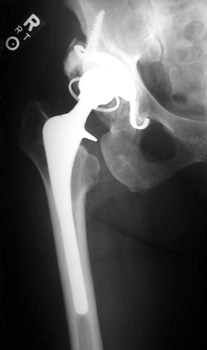

Broken, frayed, and disintegrating cerclage cables